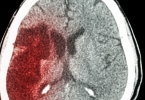

脑出血瞳孔扩大是什么意思?

脑出血如果瞳孔放大,意味着患者的预后极差。瞳孔放大是动眼神经受累的表现,脑出血患者的血肿和血肿周围的浮肿带有占有效果,占有效果明显可能引起脑疝。脑疝是指脑内组织通过生理性和非生理性的孔向其他地方移位, ...